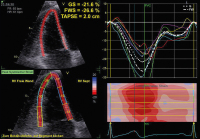

Echo

Abbildung 2: Triplane Aufnahme des linken Ventrikels mit einem 3D-Schallkopf (apikaler 4-Kammer-Blick links oben, 2-Kammer-Blick rechts oben, 3-Kammer-Blick links unten).